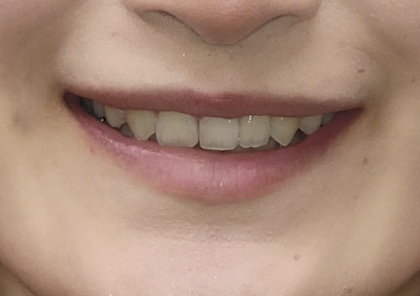

before

前歯の噛み込み「Over Bite」が深すぎて、下の歯が全く見えない状態でした。左上の犬歯が飛び足しており、口元も非常に目立っていました。

・かみ合わせが深いと思っていた。

・八重歯が出ているのが嫌だった。

・横から見て笑ってもあまり歯が見えないことが気になっていた。 -